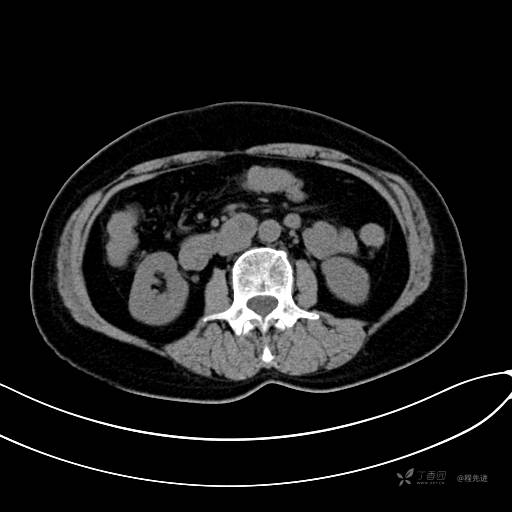

CT平扫